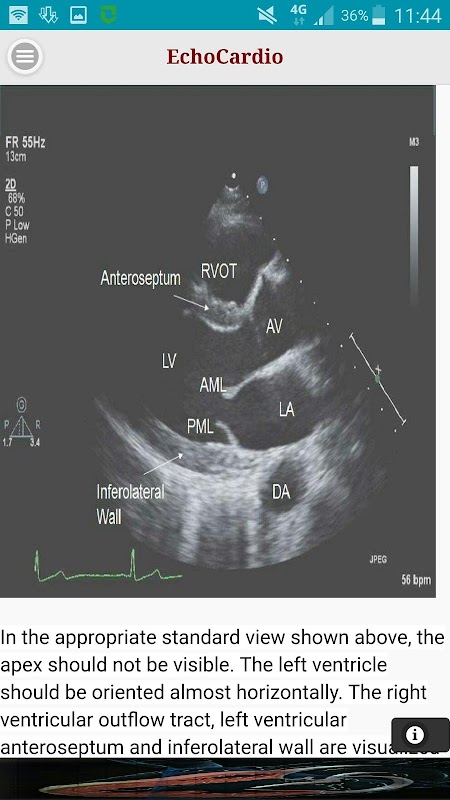

echokardiografia Przezklatkowe (TTE) są najczęściej wykonywane badanie ultrasonograficzne serca. Wysokiej jakości przezklatkowe badanie echokardiograficzne może być szybko wykonywane przy łóżku i ma potencjał, aby kompleksowo ocenić skurczową lewej i prawej komory i funkcji rozkurczowej, regionalnej kurczliwości, zastawkowej choroby serca i choroby osierdzia.

Przymostkowej długiej osi